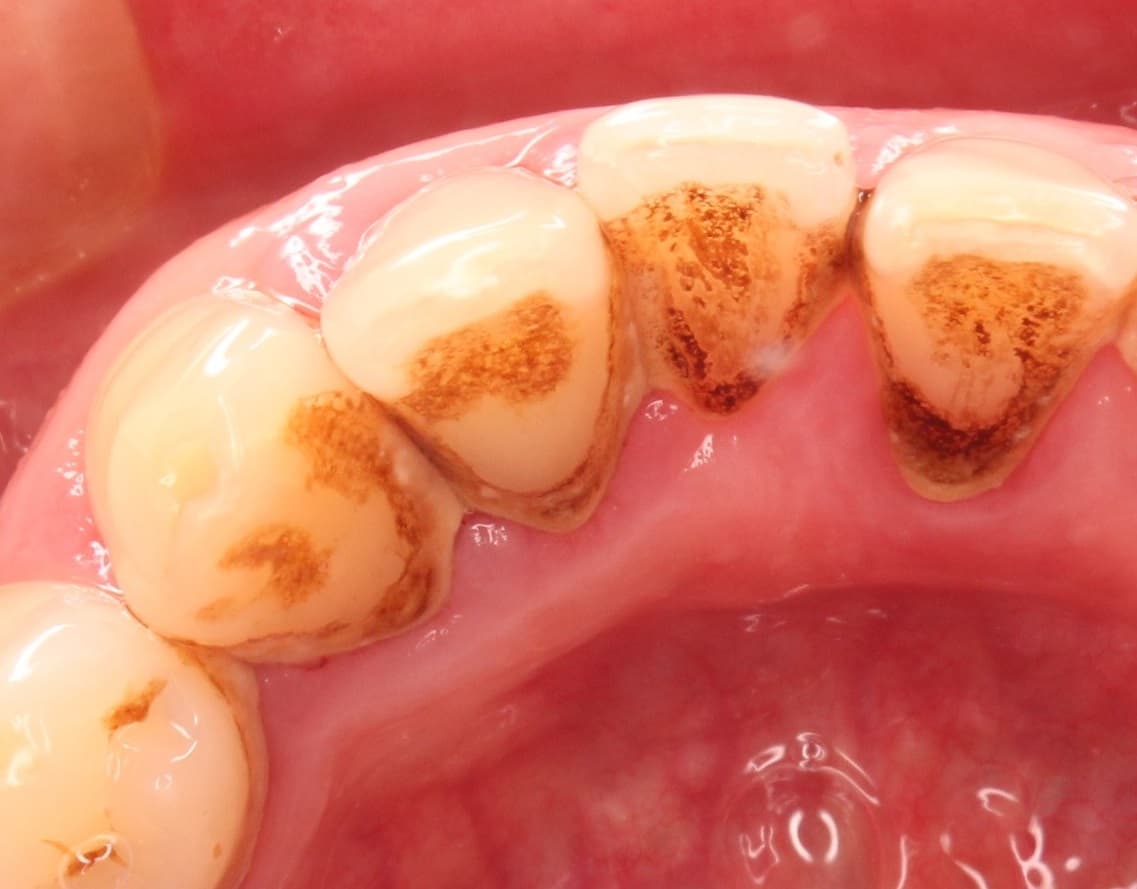

しかし、今回詳しく検査をしてみると、写真でもはっきりとわかるように、歯石やプラーク、ステインなど感染物が大量に付着しています。

歯石は、歯周病(歯槽膿漏)の直接の原因にはなりませんが、細菌の温床(住み家)にはなります。

そして、除去されるまで次々と新しい細菌が付着して、時間をかけて歯石が分厚く成長し、歯周ポケットの中まで入り込むようになります。

歯周ポケットの中(歯の根っこ周辺)で細菌感染が長い期間続くと、じわじわと歯を支える骨が失われていきます。

今回のケースはこの状態に当てはまります。

非常に頑固な歯石が大量についていましたが、歯や歯周組織がダメージを受けない様に一本ずつ丁寧に落としていきました。

こうすることで、施術後の知覚過敏や歯肉の退縮を、できる限り最小限に抑える事が出来ます。